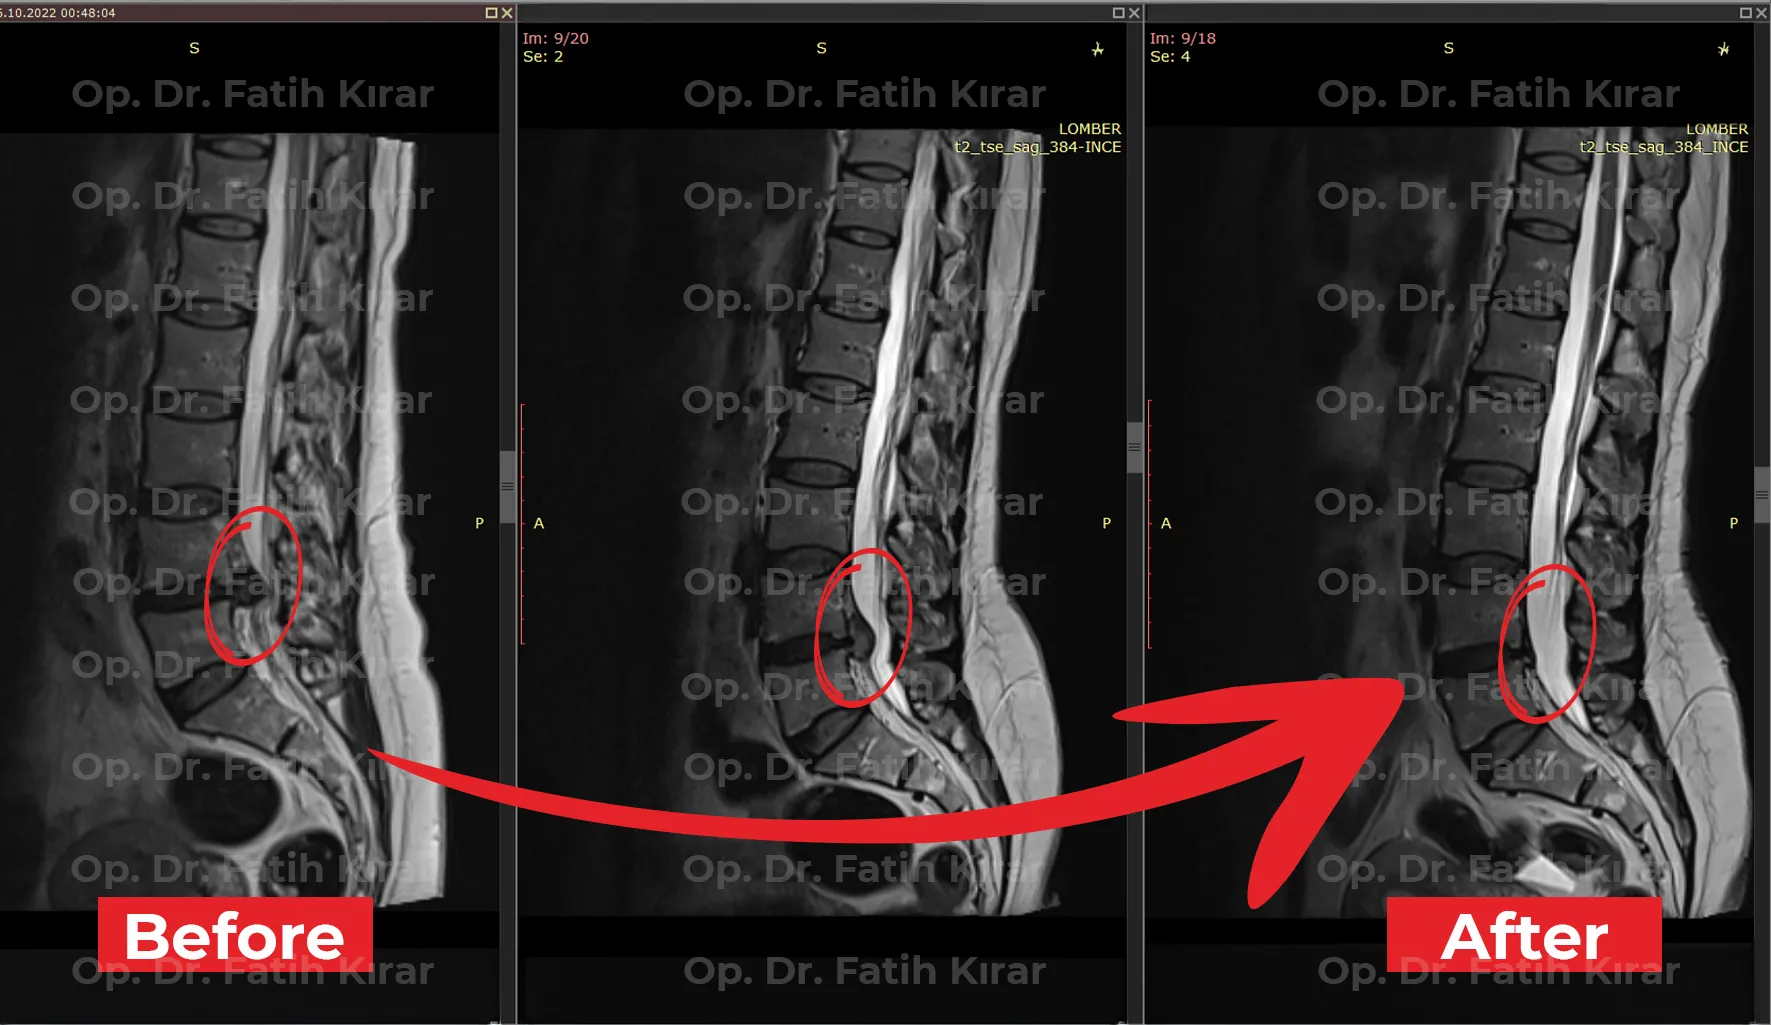

Advanced minimally invasive and non-surgical interventions with proven outcomes. MRI results demonstrating successful treatment of spinal conditions.

Spine treatment MRI comparison - Clinical outcome